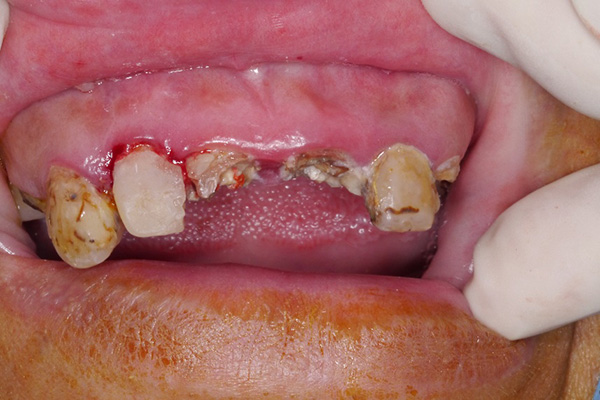

噴砂治療為牙周病及人工植體周圍炎治療前預備治療,於煙癮或者嚼食檳榔患者身上,在開始主療程前先以噴砂方式清除菸垢及檳榔垢後,露出乾淨牙根表面,再開始進行牙周病治療,提升治療成效。

紅色箭頭:(噴砂前)菸垢及檳榔垢嚴重堆積。

黃色箭頭:(噴砂後)牙齒牙根表面乾淨,醫師得以仔細檢查牙周病以及植體感染源。

*以上醫師案例僅供參考;患者應依醫師個別評估結果為準。*

雄高信合美牙醫 牙周病科呂婷醫師 臨床案例提供